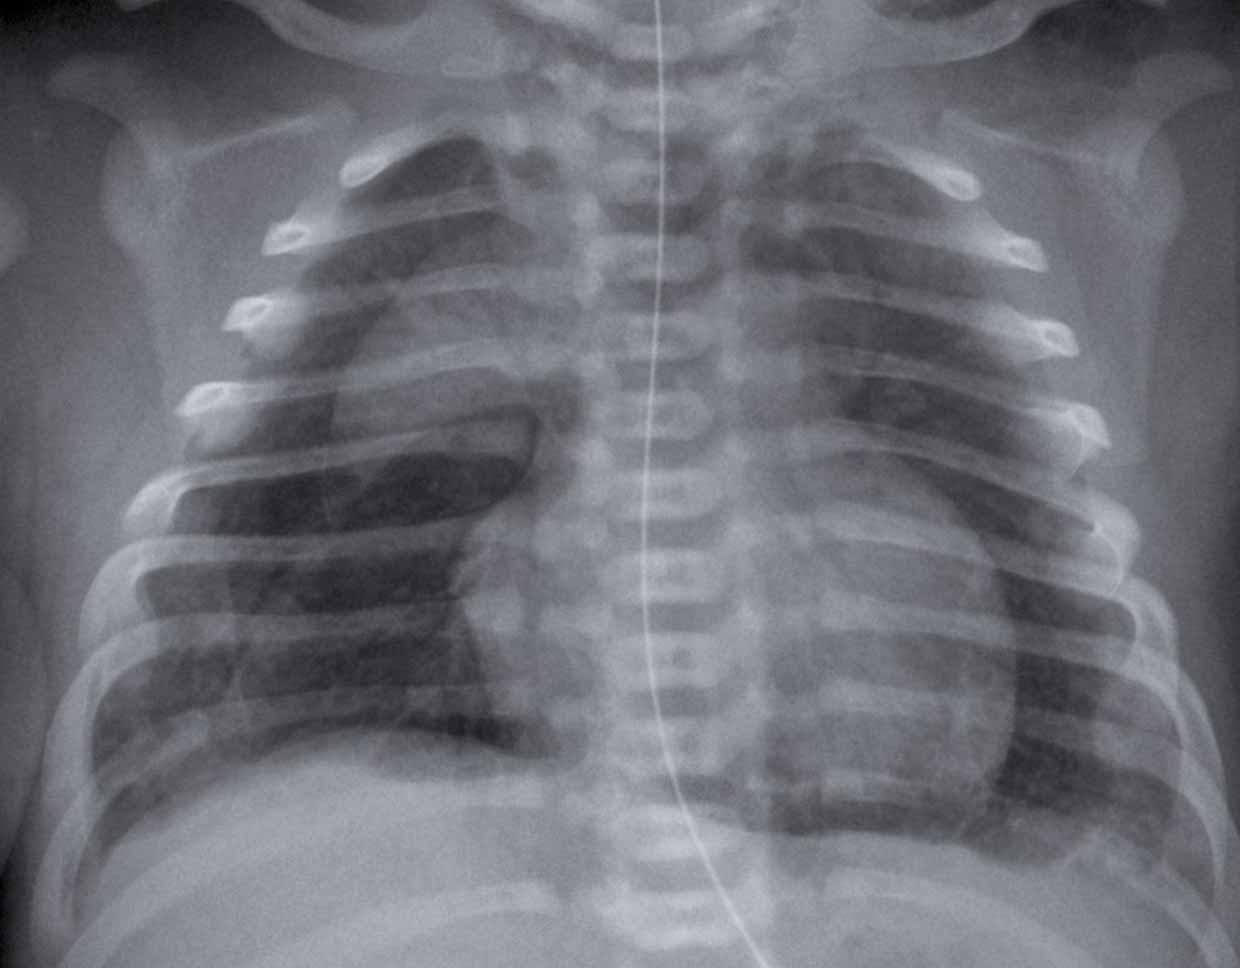

One day old neonate, 29

weeks of gestational age.

Image

- Hyperinflation due to CPAP.

- Granular opacification of

both lungs with air bronchograms. - NG tube in good position.

- Vessels and cardiac

silhouette are harder to distinguish.

Conclusion: RDS grade 2.